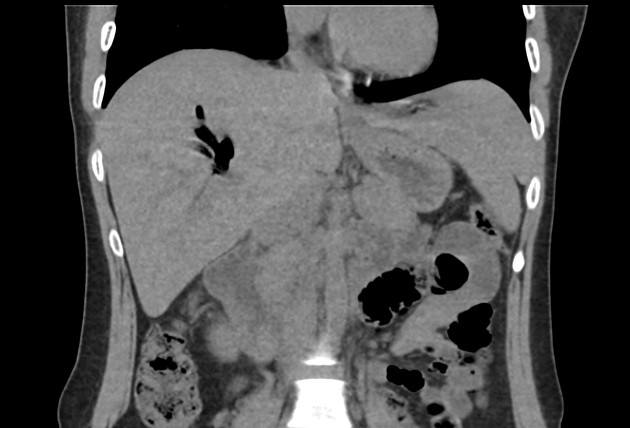

Khí đường mật

Khí đường mật - Ảnh 5

» Thông tin: Nữ giới – 30 tuổi.

» Lâm sàng: Đau mạn sườn phải / Tiền sử cắt túi mật.